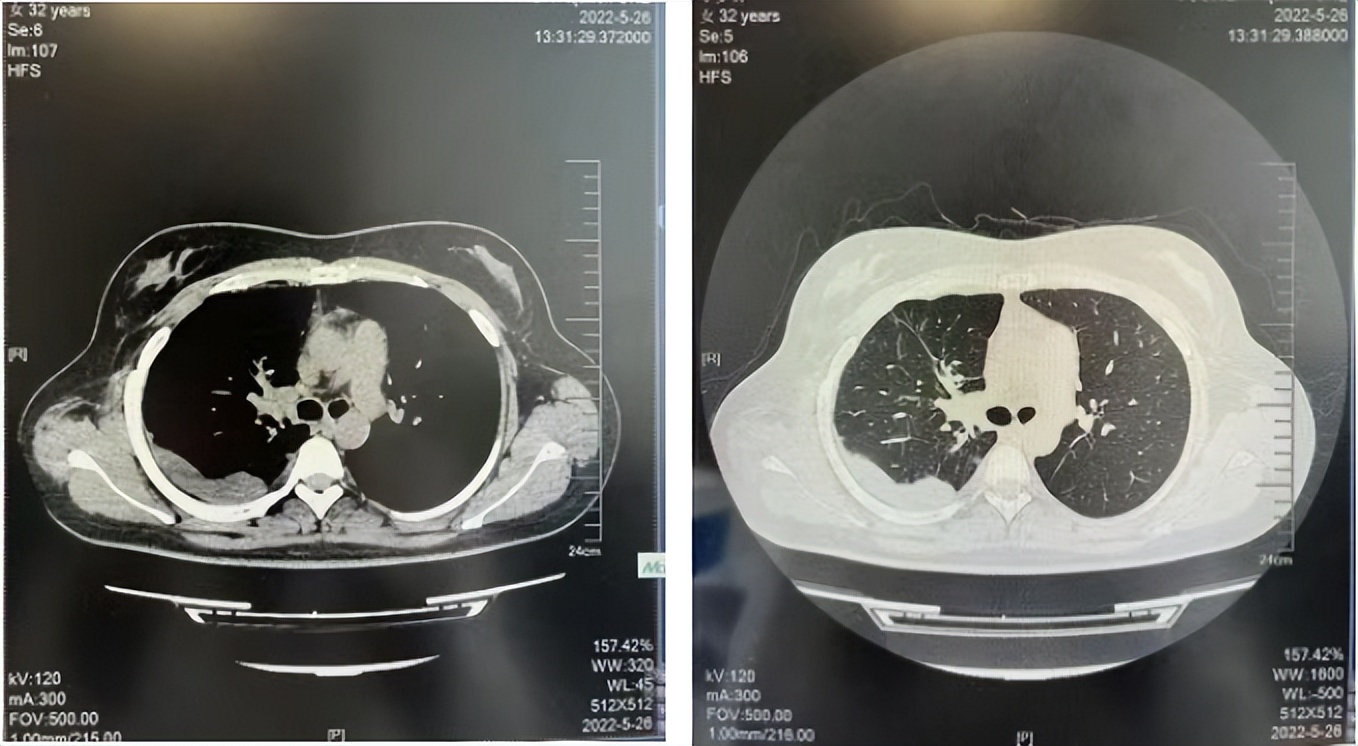

2016年1月复查CT提示支气管截断可见新发小结节,一线治疗采用培美曲塞+DDP方案化疗4周期(培美曲塞3.36,DDP 480mg)。化疗后复查胸部CT:右肺见不规则结节样影,最大层面大小约19mm*8mm,较前比较明显增大,疗效评估PD。2017.3-2017.4予单药多西他赛化疗3周期,疗效评估SD。2018年5月末复查CT提示结节较前增大,评效为PD,2018年6-10月予多西他赛+CBP化疗4周期,疗效评估SD。2022年5月患者出现活动后气短,复查胸部CT示右肺膨胀不良;右侧胸腔积液增多。胸腔积液包埋病理示符合肺腺癌细胞。行NGS基因检测:EML4:exon13-ALK:exon20融合。PD-L1(克隆号22C3)TPS<1%。

2018.07

2022.05

2022.08

2023.05